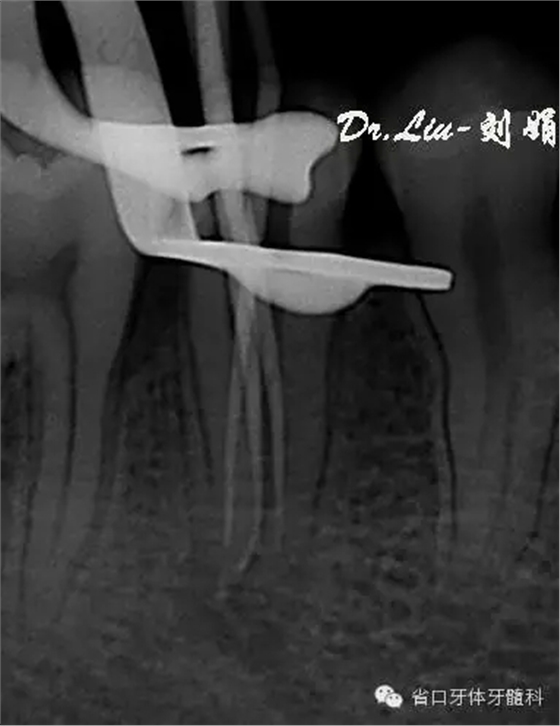

圖5:術(shù)中插尖片,見(jiàn)3根管